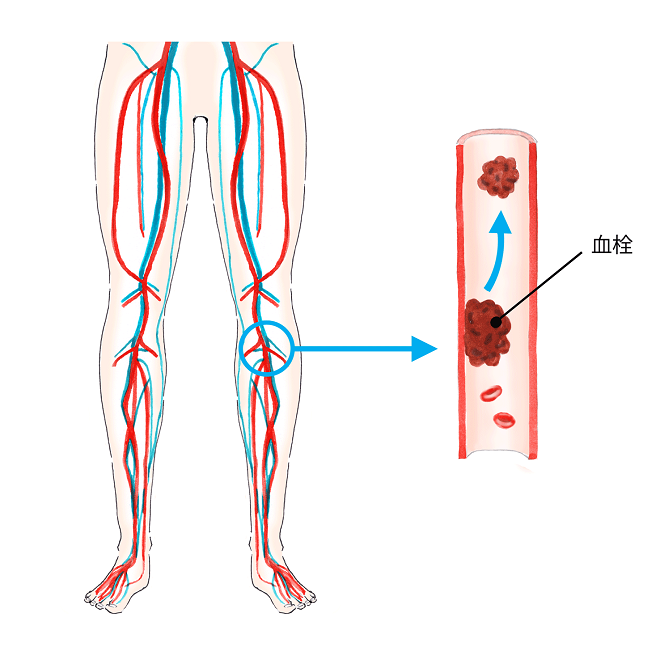

末梢血管疾患解説患者さまへイムス葛飾ハートセンタ。

深部静脈血栓症イラスト - No: 24599005無料イラスト・フリー素材なら「イラストAC」。

深部静脈血栓症イラスト無料イラスト・フリー素材なら「イラストAC」。

脚領域における深部静脈血栓症の医学的図。のイラスト素材・ベクター Image 98030310。

エコノミークラス症候群 深部静脈血栓症 メカニズムのイラスト素材29374549- PIXTA。

深部静脈血栓症イラスト無料イラスト・フリー素材なら「イラストAC」。